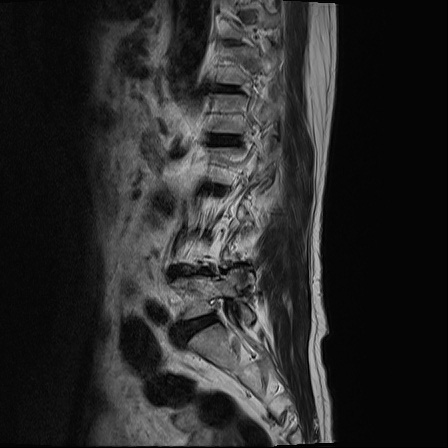

Ӵϲ ɿ ô ô 㸮 ٸ ̾ϴ. ϵ Ͻð ܻ 㸮 20⵿ ͽϴ. mri ˻ ɿ Ȳ ʹ ؼ Ȳ̶ ߽ϴ. ϻȰ ϰ 鼭 ½ϴ. ̴ ø鼭 Ͻô Ȳ ̷ ġ ص ȸ ϴ. δ Ҵµ, ù ȸԲ ˷ֽ ϰ β ϰ, ˷ֽ ü ƮĪ ϸ鼭 ȭǸ鼭 Ӵϲ ȸų ְ ǰ, β 鼭 ʴ β ؾϴ ŷο 1ϸ ijħ ڸ ǥ Ʈ ߽ϴ. ȸ ȭϽø鼭 Ϸ簡 ٸ ȸǽð 4ְ Ǿ Ǯ鼭 ¦ ҽϴ. ħ ȸ ȭϸ鼭 ڼ ü ƮĪ ϴ. ȥڼ Ͻʴϴ. ٳø鼭 ó Ͻ ʴϴ. ̾ ְ ̳ ߵ ʰ ϴ ȸԲ Ͻʴϴ. ʹ ϸ鼭 ϴ. Ȩ - ϱ ٴ Ȳ MRIԴϴ. |